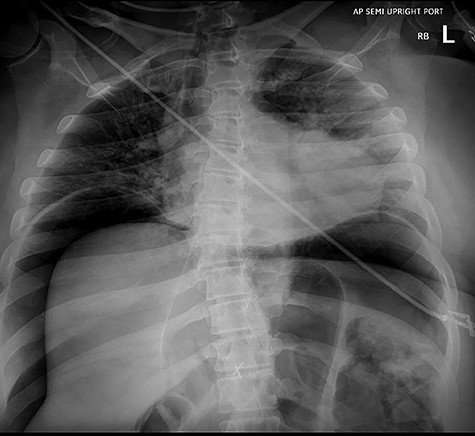

As the patient emerged from sedation, she experienced respiratory distress requiring intubation and her abdomen was noted to be distended. Abdominal X-ray revealed massive pneumoperitoneum (Fig. 3). The patient was taken to the intensive care unit (ICU) where she remained hemodynamically stable and with normal airway pressures. Attempts at Foley catheter placement in the ICU were unsuccessful. Approximately 2 h following transfer to the ICU she was taken to the operating room for exploratory laparotomy. A urologist was able to insert a Foley catheter before the operation and the bladder was noted to be empty.

Abdominal X-ray revealing massive pneumoperitoneum after endoscopy.